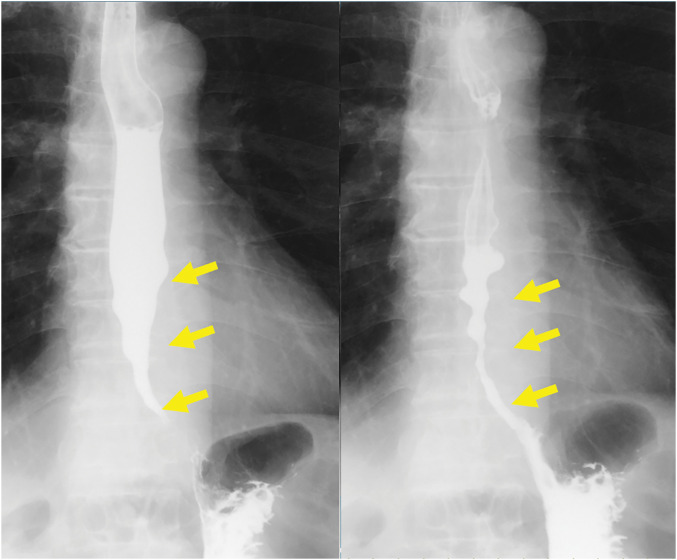

Case presentation: The patient was a 67-year-old man who was diagnosed with esophageal achalasia 13 years earlier. Partial esophagectomy of the portion with the stricture and esophago-jejunal anastomosis using the overlap method were performed for the esophageal stricture due to rupture during endoscopic balloon dilatation. The patient's postoperative recovery was unremarkable, and the dysphagia due to esophageal stricture disappeared.